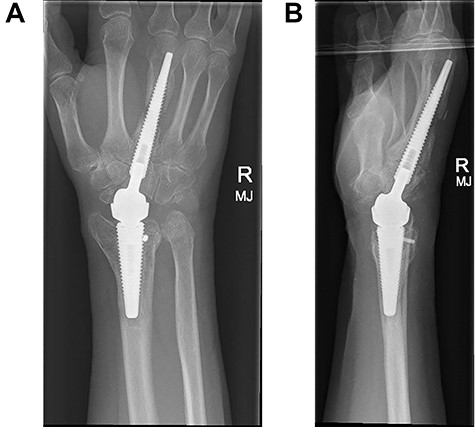

Following appropriate consultation and consent, she underwent total wrist arthroplasty. She reported complete pain relief and an improved range of movement. Ten weeks following surgery the patient presented in the emergency department following a fall. She landed heavily on the dorsiflexed hand and wrist, immediately noticing a change. Imaging confirmed that she had sustained a periprosthetic fracture in the middle finger metacarpal with dorsal displacement of the implant (Fig. 2A and B). Following a trial of non-operative treatment, she underwent revision surgery. The distal metacarpal implant was removed and replaced with a longer implant and the metacarpal fracture defect region was reinforced with autologous bone graft (Fig. 3A and B).

(A and B) PA and lateral radiographs showing a periprosthetic fracture around the metacarpal implant of a Motec wrist replacement.